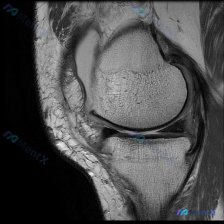

看到一个很有代表性的读片病例,整理了一下病例和分析思路分享给大家。 病例基本信息 这是一张膝关节MRI矢状位T1加权像,临床提示怀疑存在软骨异常,需要我们读片分析。 影像读片结果 先给大家说下完整的读片发现: 1. 序列与定位确认:这是标准的膝关节矢状位T1加权像,左侧为前,右侧为后,上方是股骨远端...